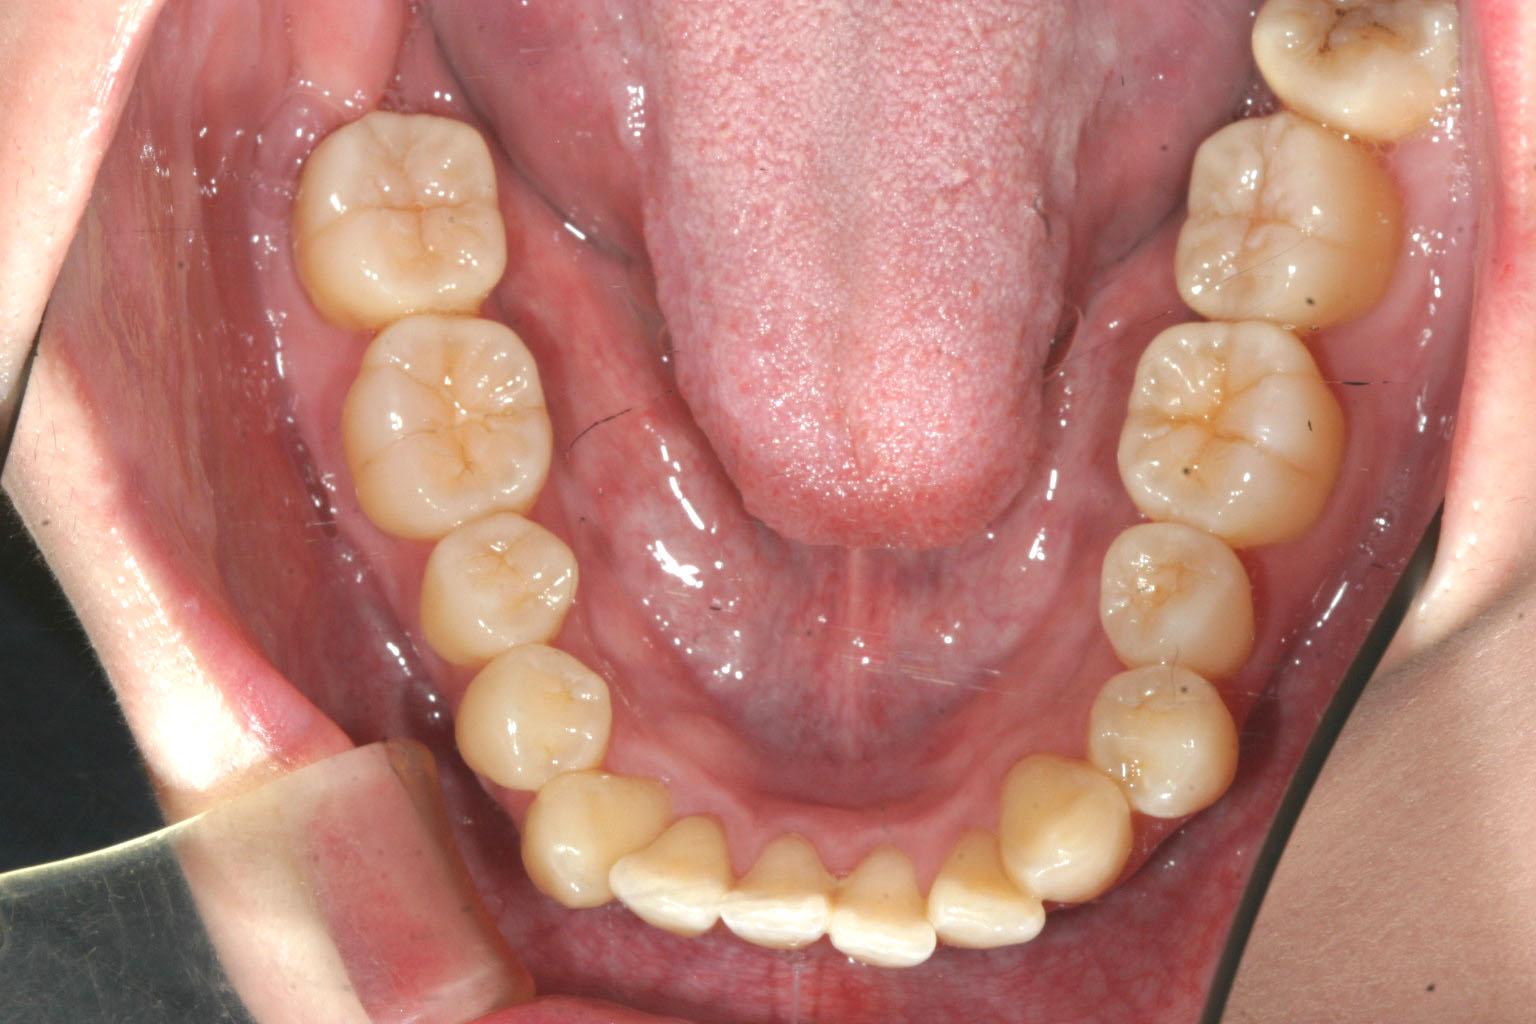

下顎のアーチも多少の前歯部にガタガタが目立つだけで大した事は有りません。